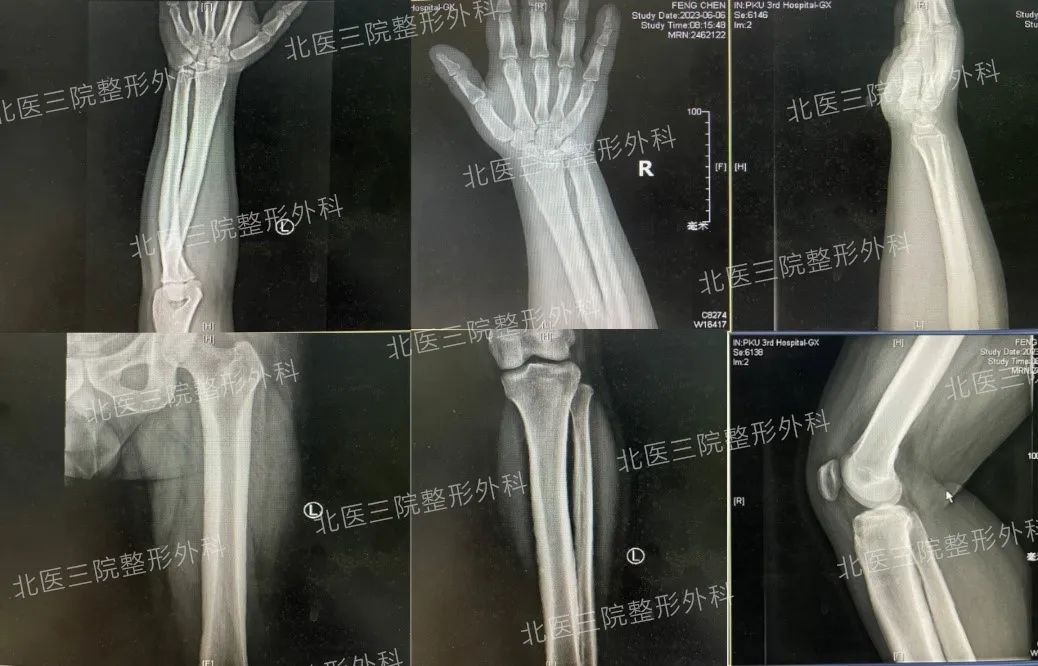

四肢X线影像

我们医生经与患者沟通了解到,患者自高中时期发病,逐渐出现面容及四肢外形改变;大学时期开始自觉双侧膝关节阵发疼痛,未口服用药。患者自述其爷爷头皮增厚沟回状改变。患者要求改善“额部皱纹”意愿强烈,遂由门诊入我科,住院后完善四肢X线检查发现患者双侧尺桡骨、双侧胫腓骨骨皮质显著增厚。除高尿酸血症,血常规、甲状腺激素、生长激素、泌乳素等未见明确异常。

综合患者发病特点、临床表现及X线表现,考虑其为“骨膜增生性厚皮病”。